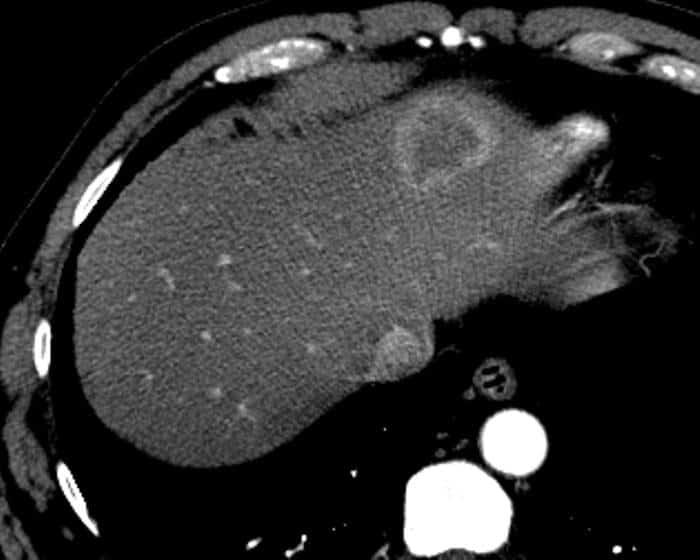

Ung thư đường mật

» Thông tin: Nam giới – 57 tuổi.

» Lâm sàng: Đau bụng.